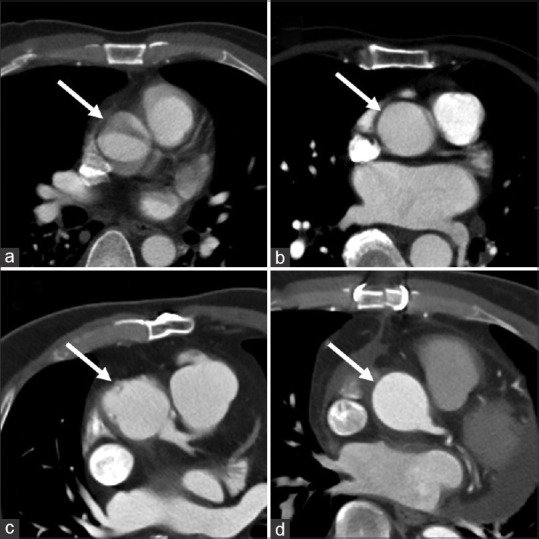

Results: The mean volume CT dose index, dose length product and effective dose in group 1 were 12.4 ± 1.9 mGy, 765.8 ± 112.4 mGy cm and 13.0 ± 1.9 mSv, respectively. These were significantly higher compared to group 2 values (9.1 ± 2.6 mGy, 624.1 ± 174.8 mGy cm and 10.6 ± 3.0 mSv, respectively) ( P < 0.001). Qualitative assessment showed the image quality at the aortic root-proximal ascending aorta was significantly higher in group 1 (median 3) than in group 2 (median 2, P < 0.001). Quantitative assessment showed significantly better mean arterial attenuation, signal-to-noise ratio and contrast-to-noise ratio in ECG-triggered CTAA compared to non-ECG-triggered CTAA.

Conclusion: ECG-triggered CTAA in a single-source scanner has superior image quality and vessel attenuation of aortic root/ascending aorta, but a higher radiation dose of approximately 23%. Its use should be considered specifically when assessing aortic root/ascending aorta pathology.